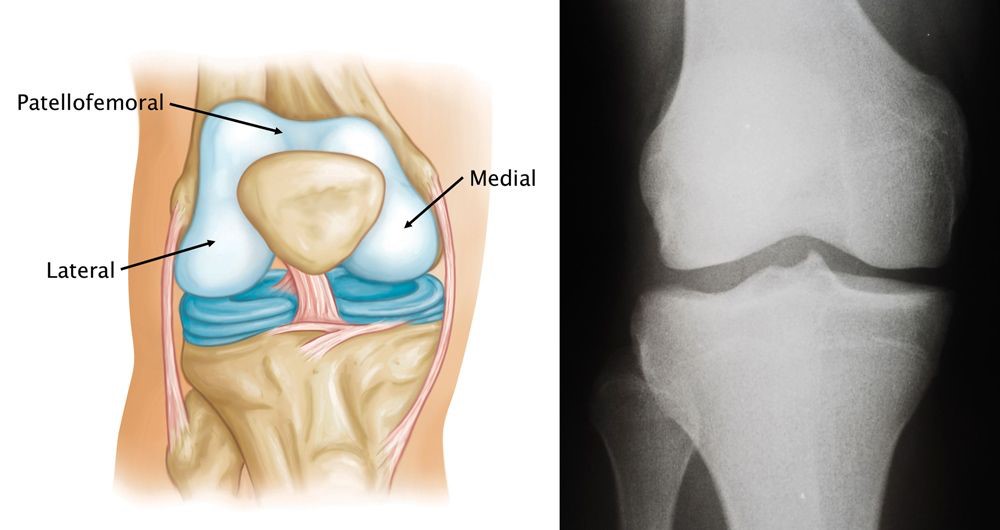

The knee joint is arbitrarily divided into three compartments for descriptive purposes:

- Medial compartment—the inside part of the knee

- Lateral compartment—the outside part of the knee

- Patellofemoral compartment—the front of the knee between the patella (kneecap) and femur (thighbone).

Within the patellofemoral compartment, the patella lies in a groove on the top of the femur called the trochlea. When you bend or straighten your knee, the patella moves up and down within this trochlear groove. Articular cartilage covers the ends of the femur, trochlear groove, the underside of the patella, and the upper surface of the tibia, and this allows movement of the joint.